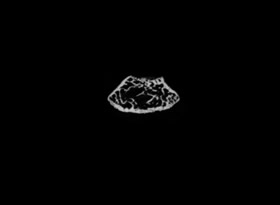

使用MicroCT可以詳細了解牙根管的三維形態(tài),測量根管的高度、體積、截面積、管壁厚度等。

1骨組織樣本掃描。

2提供2D圖、3D圖和相關(guān)參數(shù)的分析數(shù)據(jù)(骨密度BMD 單獨收費)。